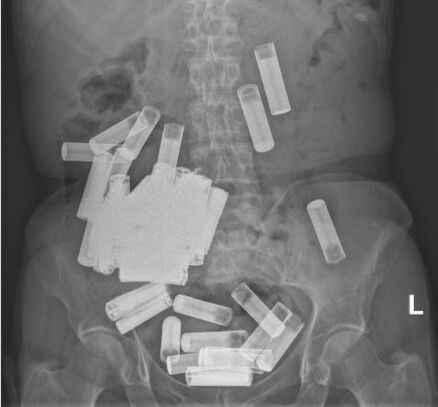

وكشف التقرير الطبي الصادر من مستشفى “سانت فينسيت” في دبلن، أن الأشعة السينية التي تم إجراؤها للمريضة، أظهرت وجود عدد كبير من البطاريات ذات الأصناف المختلفة في المعدة والقولون، ولكن من حسن حظ المرأة أنها لم تعطل عمليات الجهاز الهضمي، ولم تتسرب محتوياتها بما يضاعف من الخطر.

غير أن المشكلة التي واجهت الأطباء أن البطاريات لم تتحرك نحو الجهاز الهضمي بغرض التخلص منها بطريقة طبيعية، لذلك تم اتخاذ قرار بإجراء عملية جراحية لإزالة البطاريات، حيث تم اكتشاف أن معدة المريضة قد أصيبت بالانتفاخ.

وتمكن الجراحون من إزالة ما مجموعه 46 بطارية من بطن المسنة، بينما تم “حلب” أربع بطاريات أخرى كانت موجودة في القولون في المستقيم وإزالتها “باستخدام ضام الشرج وملقط طويل.